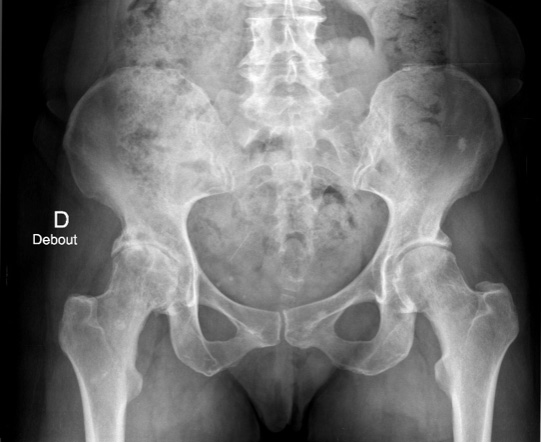

Destruction progressive du cartilage de l'articulation coxo-fémorale. Principale cause de remplacement prothétique de la hanche, elle entraîne douleurs mécaniques, raideur et limitation fonctionnelle.